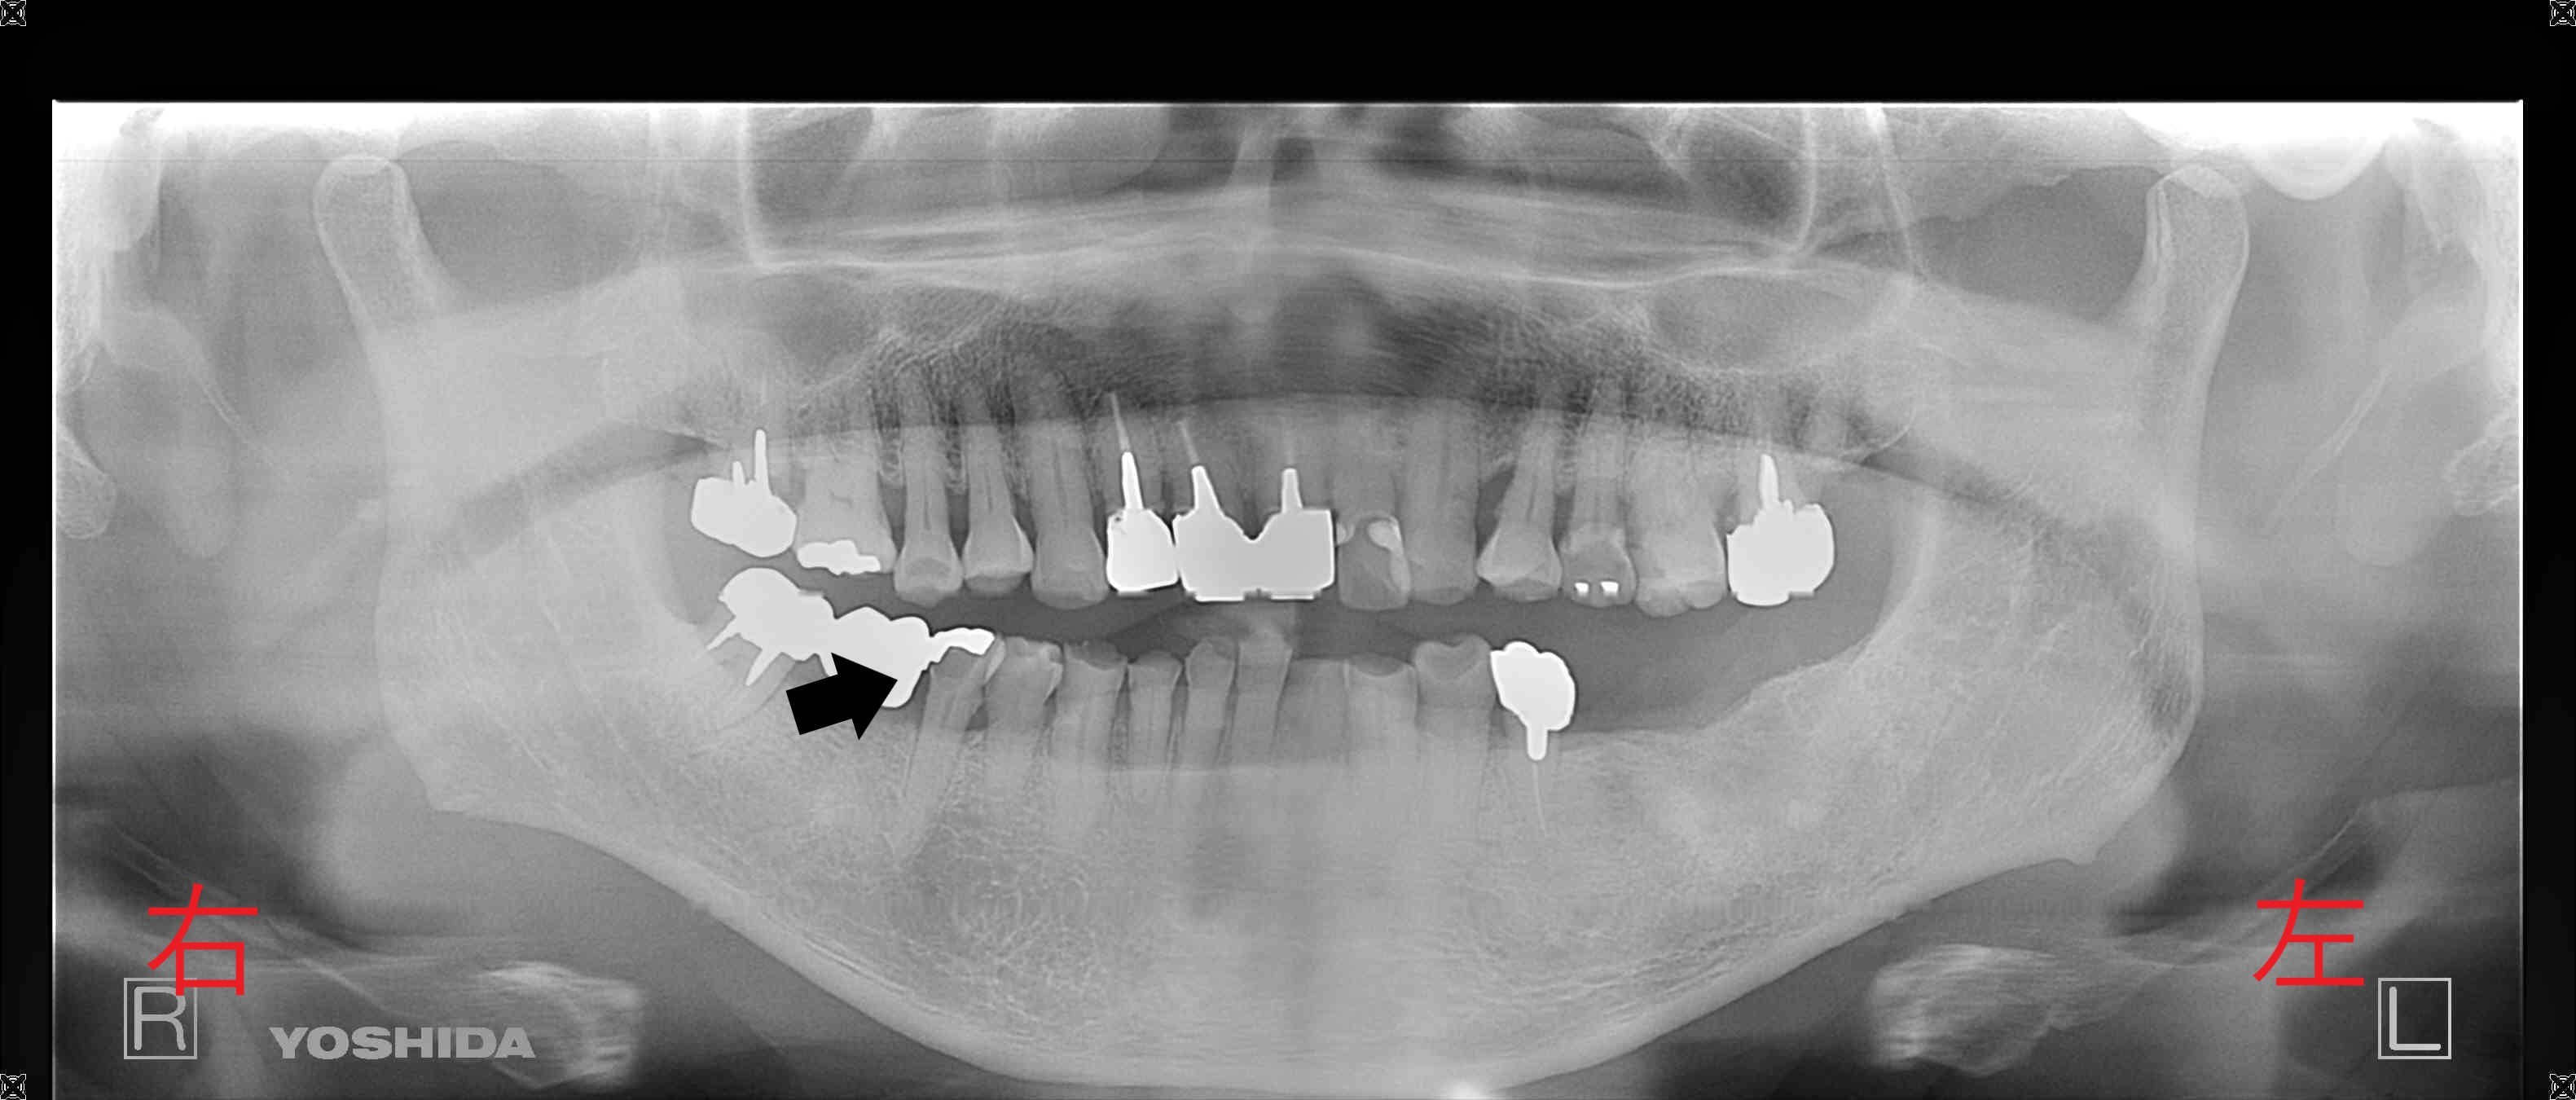

左側が初診時の治療前のレントゲン写真です。右下のブリッジという被せ(冠)がグラグラして噛めないと訴えられていた部位の黒色矢印をご覧ください。被せの下に黒い透過像が確認されており、これは歯髄(神経と血管)まで進行した大きな虫歯である可能性があります。麻酔後ブリッジを外したところ、後ろの歯根が完全に割れておりました(泣)…。

長期間、左下奥歯を欠損状態で過ごされていたため、右側の奥歯に大きな負担がかかっていたようです。歯髄の治療が必要でしたが、前方の歯(黒色矢印)は救うことができたのは幸いでした。

右側は治療終了後のレントゲン写真です。黄色矢印の歯が、インプラントを埋入した部位です。